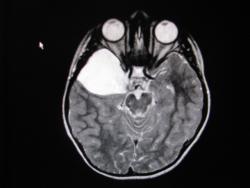

Крупная арахноидальная киста правой височной области.

да, до этого мальчик жалоб не предъявлял. наверное киста увеличилась, масс-эффект на прилежащие струкутры усилился , появилась клиника.

Да, это врожденная арахноидальная киста.